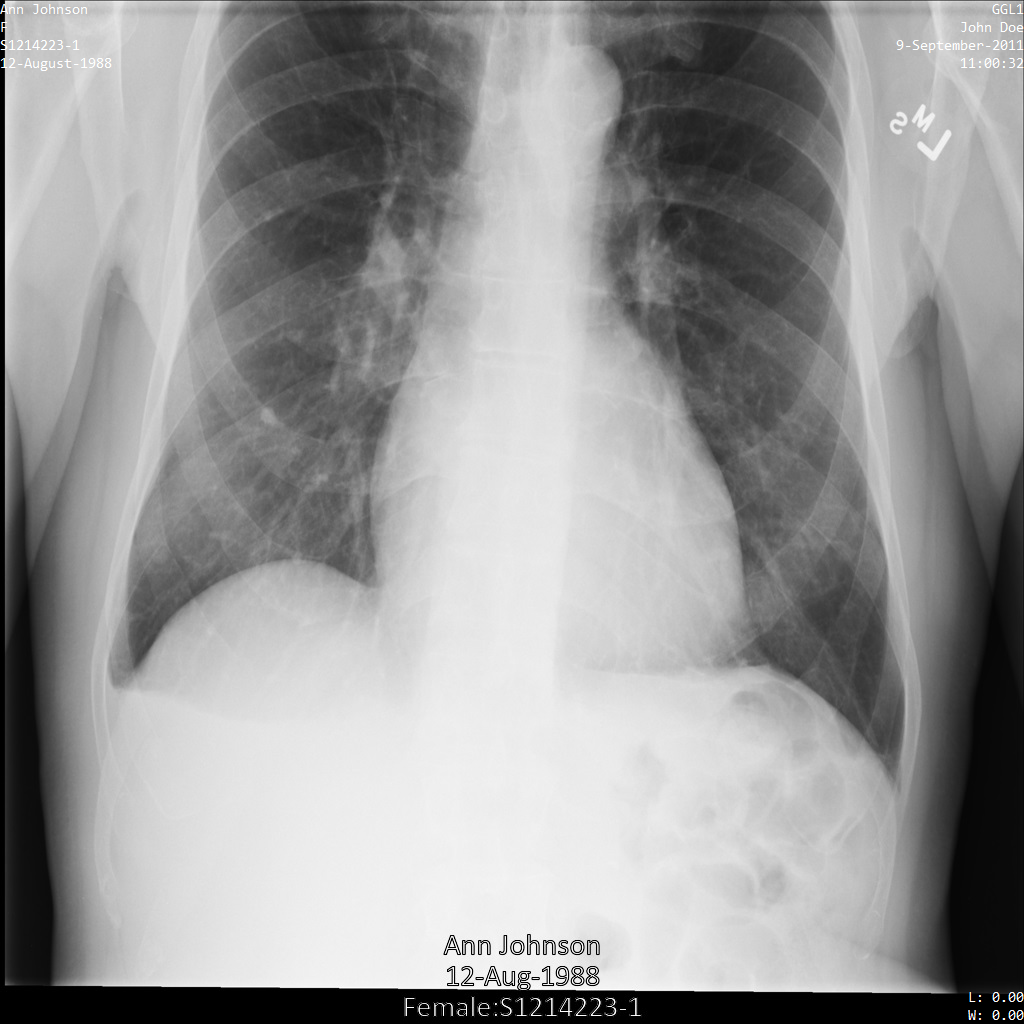

L'image suivante montre une radiographie non masquée d'un patient :

xray2_unredacted

Une fois l'image envoyée à l'API Cloud Healthcare à l'aide de l'option REDACT_SENSITIVE_TEXT, elle apparaît comme suit :

xray2_redact_sensitive_text

Vous pouvez constater que les événements suivants se sont produits :

• Le paramètre PERSON_NAME en bas à gauche de l'image a été masqué.

• Le paramètre DATE en bas à gauche de l'image a été masqué.

Le sexe du patient n'a pas été masqué, car il n'est pas considéré comme du texte sensible selon le paramètre infoTypes DICOM par défaut.